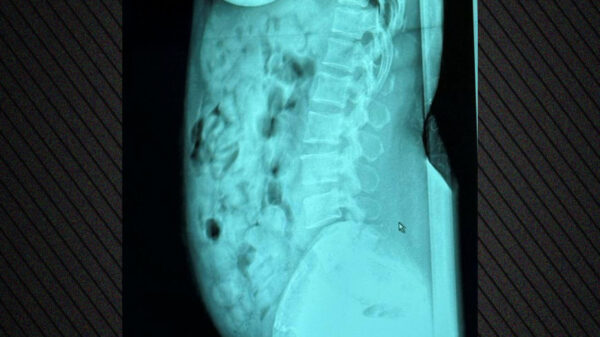

Ekzaminimet me rreze X në spitalin e Bergamos konfirmuan praninë e drogës, e cila ishte e mbështjellë me shirit ngjitës.